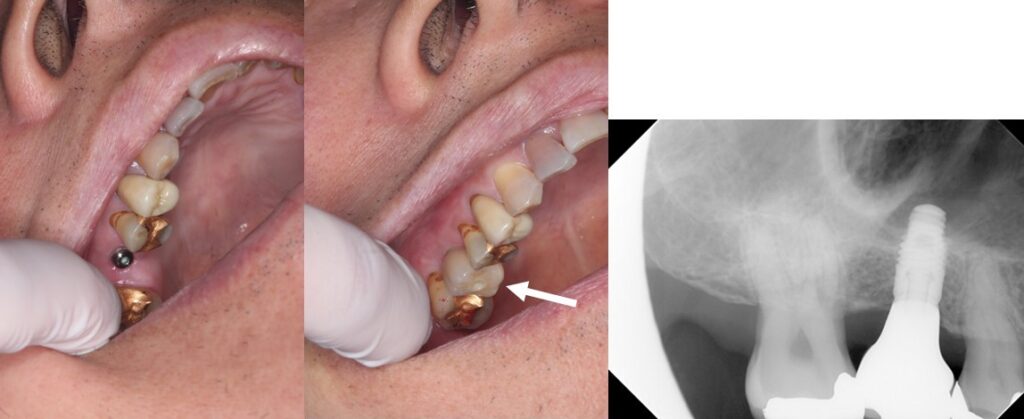

症例集

天然の歯と同様の機能と審美性